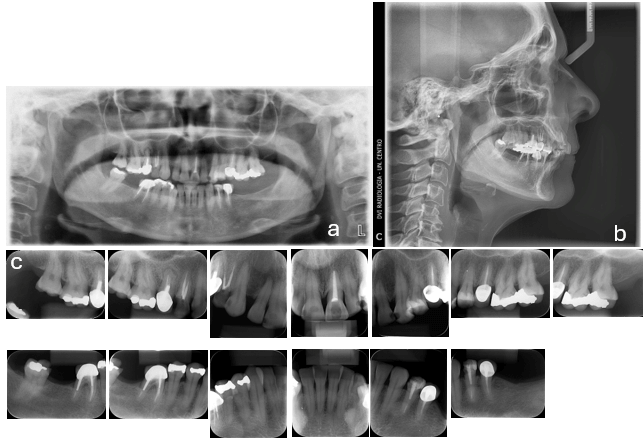

En la radiografía panorámica se observan contornos óseos regulares, las piezas dentarias 1.5, 1.4, 2.1, 3.4, 3.5 y 4.6 con endodoncia y coronas en unidades dentarias 1.5, 3.5 y 4.6 e imagen radiolúcida apical en la 1.5 de posible lesión previo al tratamiento de conducto, imagen radiopaca compatible con amalgamas en dientes 2.5, 2.6, 2.7 y 4.8. (fig. 3a)

En la telerradiografía lateral paciente Clase II esquelética, normodivergente, incisivos superiores retroinclinados e incisivos inferiores protruidos y proinclinados. (fig. 3b)

En la periapical total se observa dilaceración de raíces de 1.6, perdida parcial de corona en 1.4 y 3.4, imágenes radiolúcidas en distal de piezas 1.3, 1.1, 2.2 y mesial en unidad dentaria 2.3, imágenes radiopacas compatibles con amalgamas en unidades 1.6, 2.6, 2.7, 4.4, 4.5 y 4.8. (fig. 3c)

Figura 3.- Radiografías Iniciales

a) Panorámica b) Telerradiografía lateral c) Periapical total